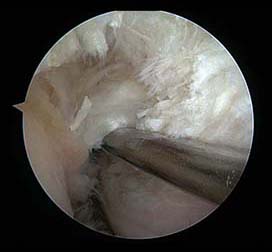

b. 전방십자인대 재건술: 환자본인의 이식물, 동종(다른 사람의 것) 이식물, 인공 인대를 이용하여 재건할 수 있는데 인공 인대는 결과가 좋지 않아 거의 사용하지 않고 자가건을 채취하는 경우 슬개건, 슬건, 대퇴사두건을 일부 채취하여 사용합니다. 이 때는 건을 채취하는 다른 수술창이 있고, 슬개골 골절이나 떼어낸 근력의 약화가 초래될 수 있고 채취 부위 통증이 있으나 인대의 회복력은 좋습니다. 다른사람의 건을 대신 사용할 수 있는데 이것을 동종건이라고 하고 감마선 조사와 70°이하로 냉동시켜 보관하기 때문에 세균 감염은 없습니다. 이 동종건을 사용할 시에는 다른 수술창이 없고 수술시간이 짧고, 정상 건을 떼어낸데 따른 후유증이 없으며 수술 후 통증이 적은 장점이 있으나 비용이 약간 더 들고 바이러스 질병전파 가능성, 거부반응, 이식건의 치유력의 단점이 있습니다. 에이즈같은 바이러스 질병 전파는 이 이식물을 채취하기전 공여자의 질병상태를 확인한 후에 채취하여 바코드로 관리하므로 현실적으로는 거의 가능성은 없다고 봅니다.